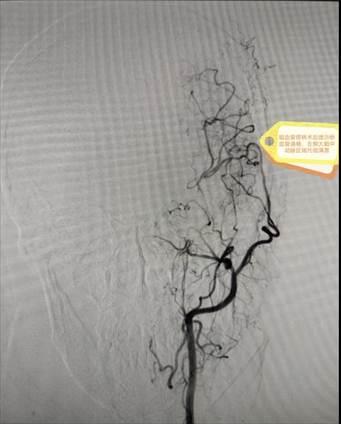

患者李阿姨3年前确诊左侧颈内动脉起始部闭塞,伴有左侧大脑中动脉M1段烟雾状改变及右侧颈内动脉眼段动脉瘤。由于病情稳定,无明显症状,未达到手术指征,初期采取密切随访观察。202512日,李阿姨前来复查时DSA显示右侧眼段动脉瘤增大,诊断为“烟雾病综合征、左侧颈内动脉闭塞、右侧眼段动脉瘤”。面对颅内外血管多发病变与动脉瘤进展的双重威胁,手术难度与风险极高,家属一度陷入焦虑。

术前DSA结果